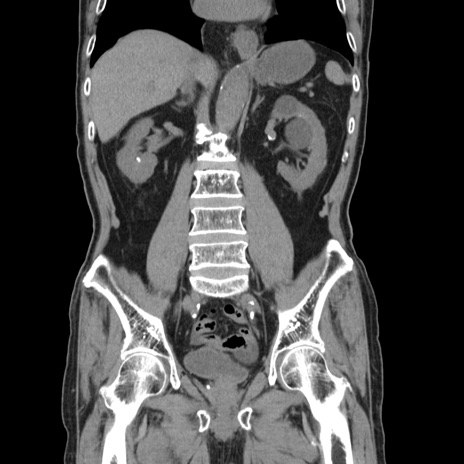

症例24(冠状断像)

【症例】80歳代男性

【主訴】左側腹部痛、嘔吐

【現病歴】本日早朝より左腹部に痛みあり。昼頃嘔吐認めたため、救急要請。

【既往歴】直腸癌(Mile手術)、胆摘

【身体所見】意識清明、BT 35.9℃、BP 221/93mmHg、SpO2 97%(RA) 、腹部:左ストーマ周囲に限局性の腹部膨隆あり。 膨隆部自発痛・圧痛あり・軟。

【データ】WBC 7700、CRP 0.09